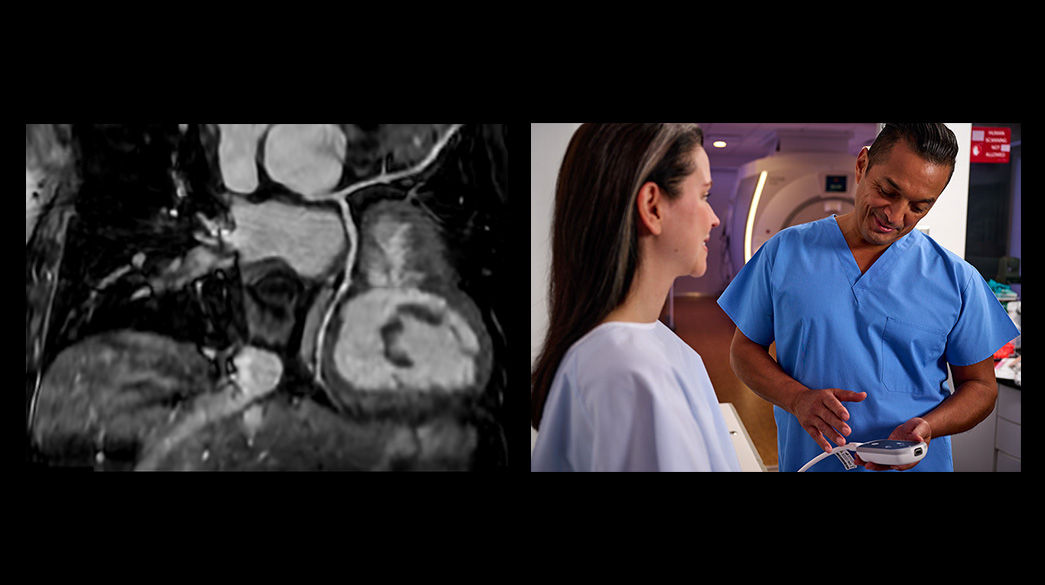

Personalized

Accommodates the individual characteristics and needs of each and every patient

AIR™ Coil

Representing a new standard in MRI coil technology, AIR™ Coils enable a simplified, faster workflow while maintaining excellent image quality.

Wireless Gating

Innovative triggering tool with the driver not attached to the gantry, giving you more flexibility and improved workflow